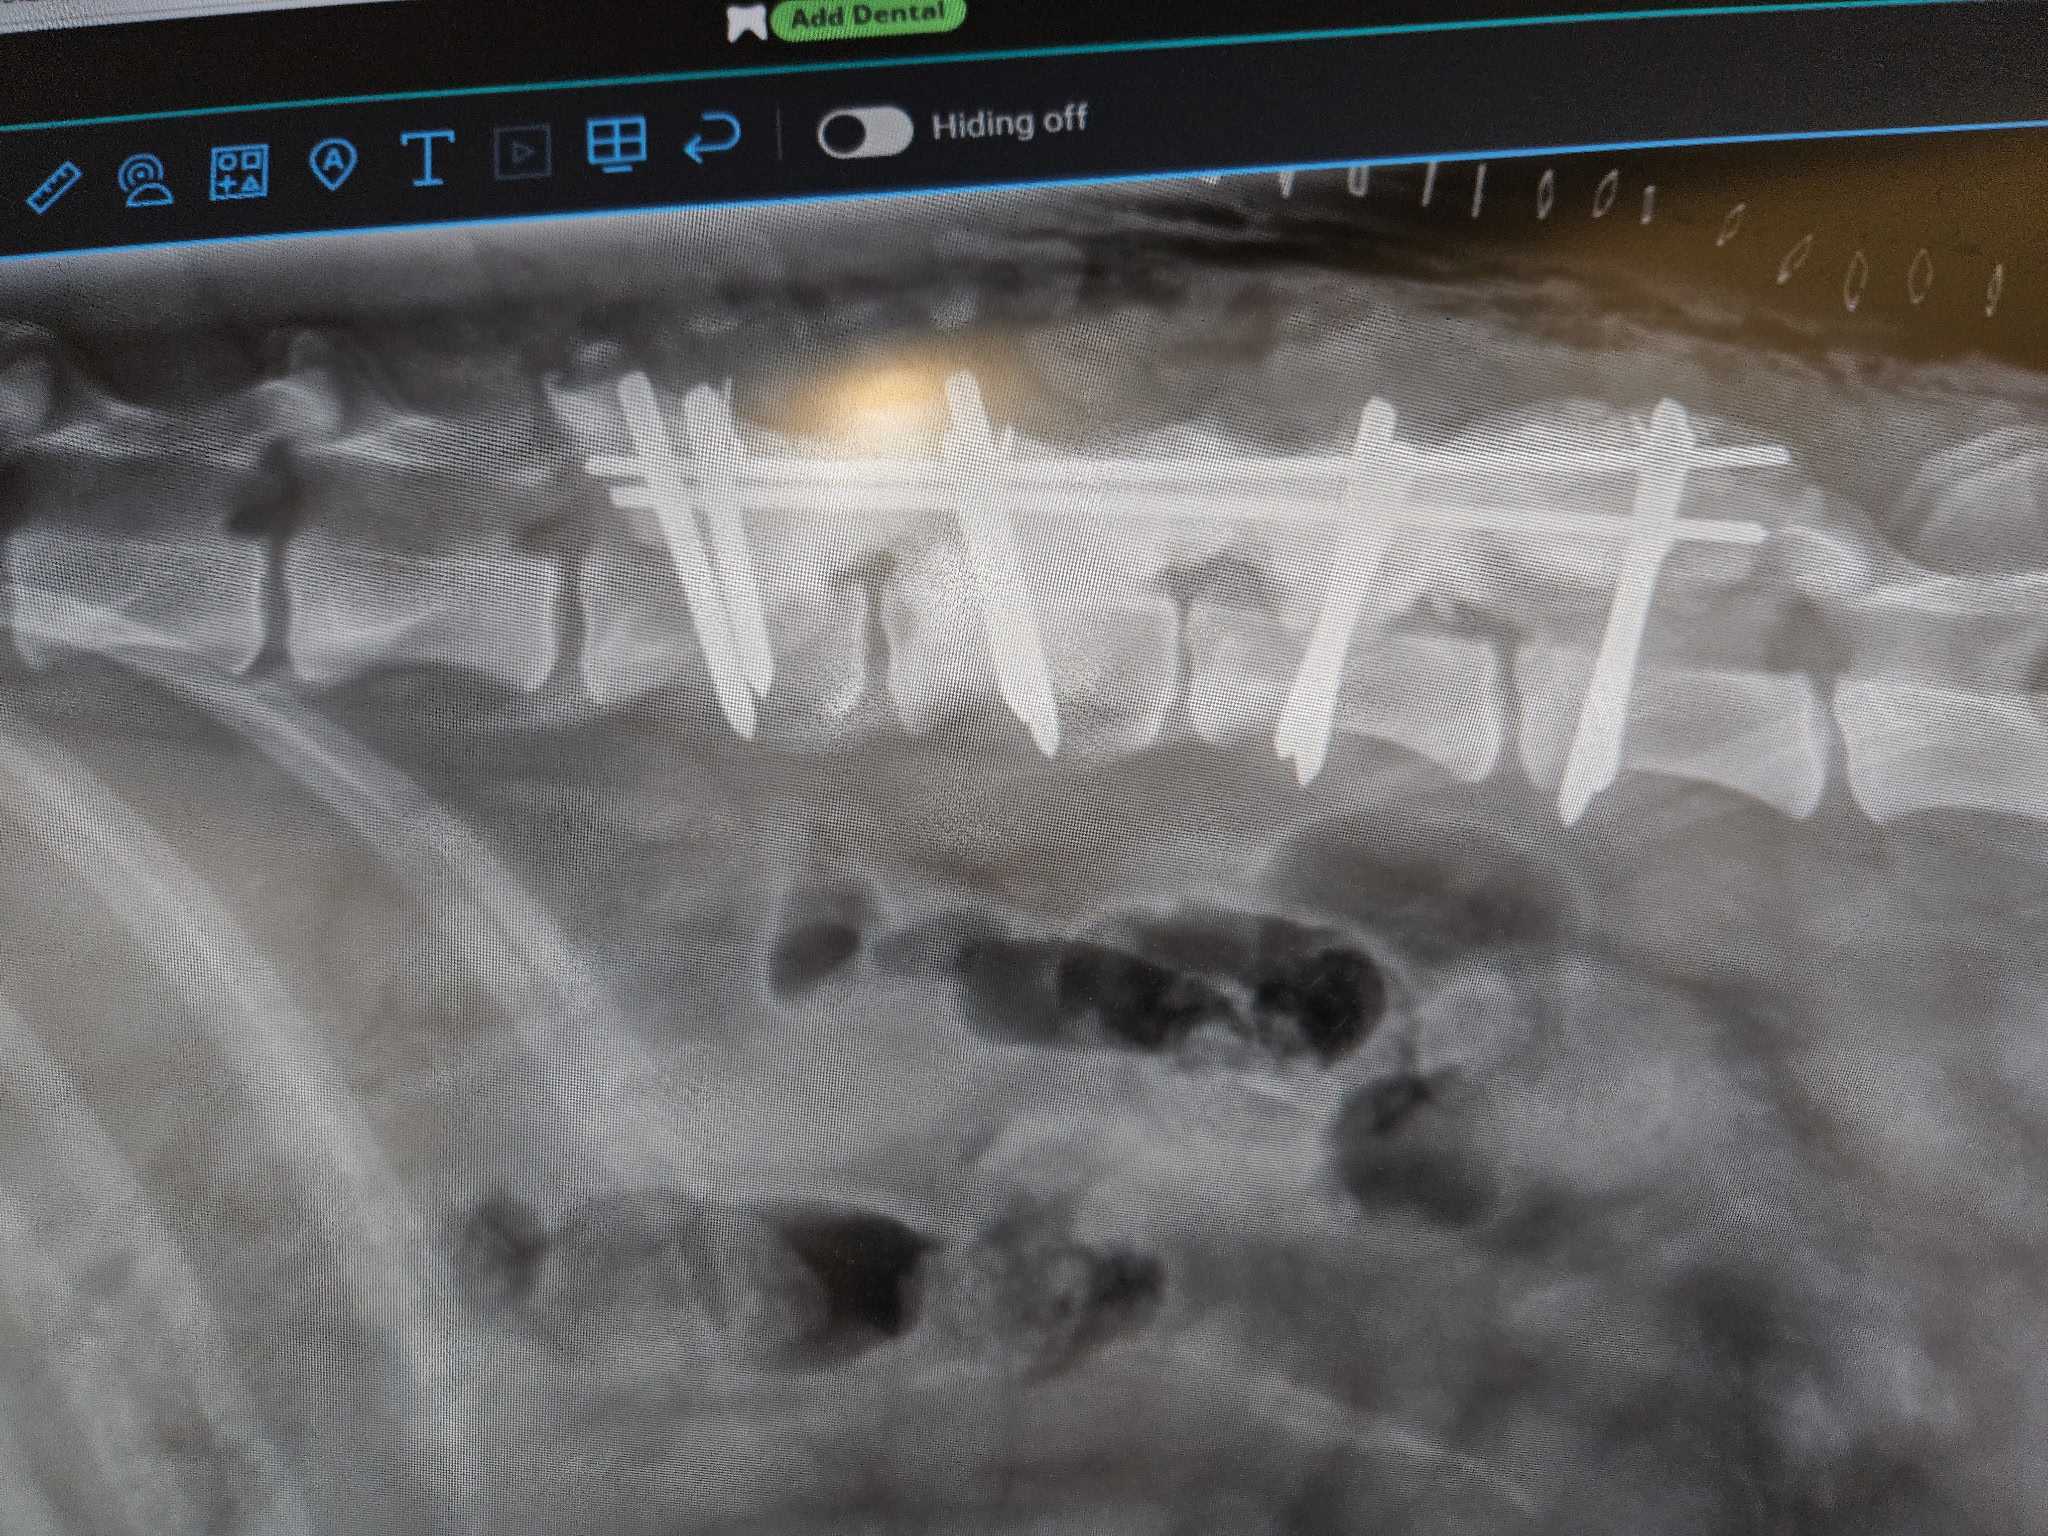

One notable beneficiary of Dr. Vetter’s donation this holiday season is Noel, a dog that was hit by a car and required urgent back surgery. Thanks to the Goochland Pet Lovers, Noel's surgery was successfully performed at Partner Veterinary Clinic. She is now recovering in a veterinary rehabilitation clinic, funded partially by Dr. Vetter’s donation.

Noel xray 2Noel xrayNoel 1Noel 2Noel 3 Dr. Erica Ditzler and NoelNoel 5Noel 6 Noel at Partner Veterinary